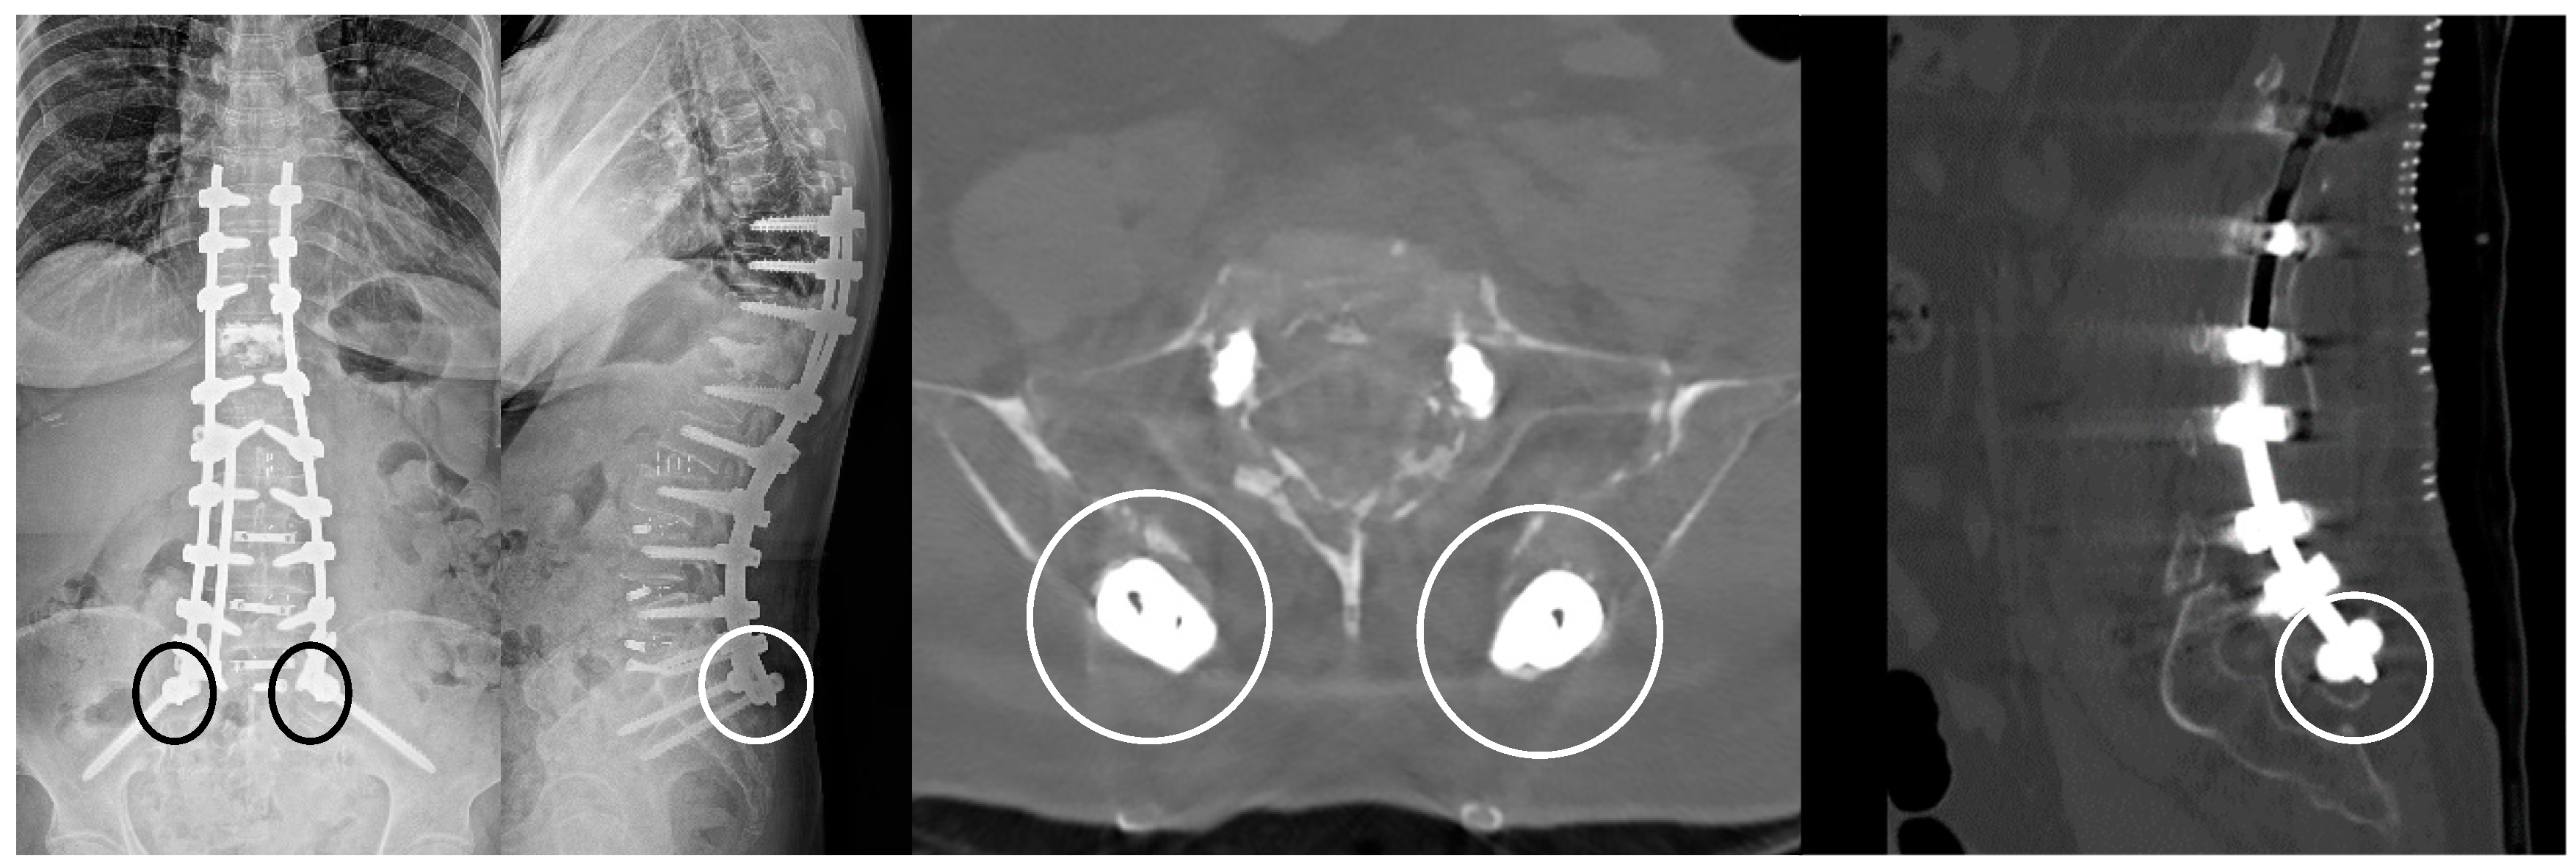

- Wang, M.Y.; Williams, S.; Mummaneni, P.V.; Sherman, J.D. Minimally invasive percutaneous iliac screws: Initial 24 case experiences with CT confirmation. Clin Spine Surg 2016, 29, E222–E225. [Google Scholar] [CrossRef] [PubMed]

- Liu, G.; Hasan, M.Y.; Wong, H.K. Subcrestal Iliac-Screw: A technical note describing a free hand, in-line, low profile iliac screw insertion technique to avoid side-connector use and reduce implant complications. Spine (Phila Pa 1976) 2018, 43, E68–E74. [Google Scholar] [CrossRef] [PubMed]